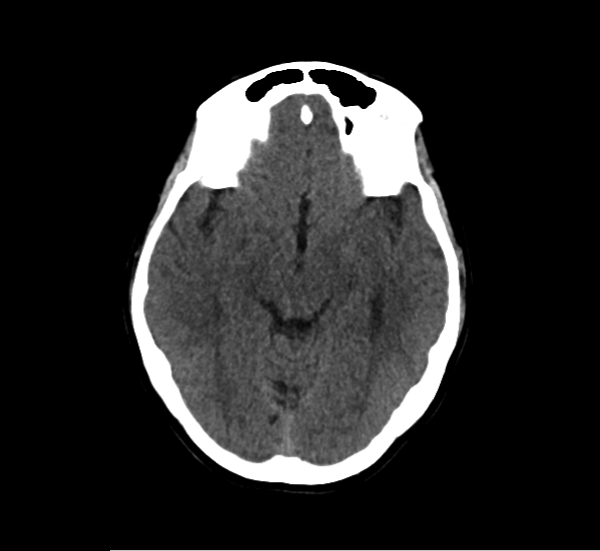

CT Brain Anatomy